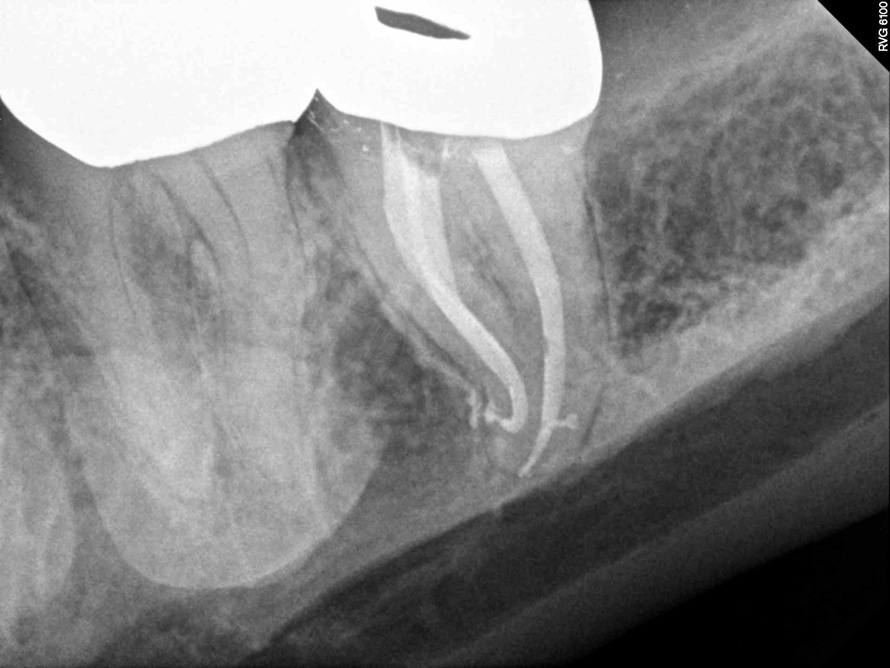

Fig 7. Cases treated by the continuous wave of condensation technique using gutta percha and epoxy resin sealer.

Fig 8. Cases treated by the continuous wave of condensation technique using gutta percha and epoxy resin sealer.

A version of warm vertical compaction, termed the continuous wave of condensation, is one of the most widely utilized obturation techniques19 (Figure 7 and Figure 8). This method involves placement of a single, tapered gutta percha cone fit to the same size as the master apical file with sealer, and downpacked with a controlled electric heat source. Based on the rotary instrumentation system used, either 04 or 06 tapered, ISO standardized apical size gutta percha cones corresponding to the final size and shape of the prepared canal can be placed with an appropriate sealer. A plugger heated to 200°F is introduced into the apical third of the root as determined by the working length to condense the apical portion of gutta percha. The heating element is turned off but left in place for an additional 5 seconds to allow slight cooling before a quick burst of heat. The heating element is removed with the coronal portion of excess gutta percha. Following this, the remainder of the canal space is filled using flowable gutta percha delivered via a motorized backfill device to the level of the chamber floor. This method can be hybridized with lateral compaction, in which spreaders are used to add accessory cones, when the shape of the canal does not allow for a tight fit of the ISO sizes of gutta percha points.